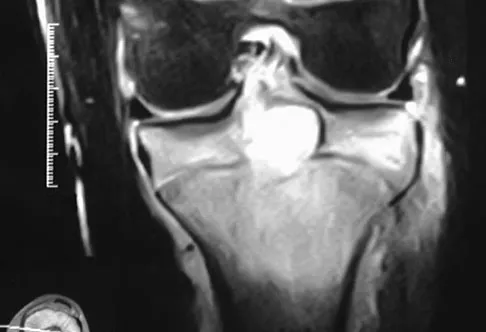

Figure 22 shows the MRI scan of a 20-year-old female basketball player who has pain over the anterior knee that interferes with her performance. Examination reveals phase III Blazina patellar tendinosis. Management should consist of

Explanation

Excision of the affected mucoid degenerative area is considered appropriate management in the Blazina classification system. A finding of phase III indicates persistent pain with or without activities, as well as deterioration of performance. With the appearance of the mucoid degeneration and the vigorous activity level of the intercollegiate basketball player, it is unlikely that nonsurgical management will provide adequate relief. When excising the affected degenerative area, care must be taken to retain normal tendon fibers. The defect in the patellar tendon is closed with absorbable sutures, as is the paratenon. Postoperative rehabilitation involves initial mobilization extension, with progressive range-of-motion and mobilization exercises as tolerated and weight bearing as tolerated. Open chain and isokinetic exercises are delayed until full range of motion and mobility is obtained, generally within 4 weeks. A return to activities is achieved by 80% to 90% of athletes, although there may be occasional activity-related aching for 4 to 6 months after surgery. Blazina ME, et al: Jumper's knee. Orthop Clin North Am 1973;4:665. Kelly DW, Carter VS, Jobe FW, Kerlan RK: Patellar and quadriceps tendon ruptures: Jumper's knee. Am J Sports Med 1984;12:375-380. Krums PE, Ryder B: Operative treatment of patella tendon disorders. Operative Techniques Sports Med 1994;2:303.